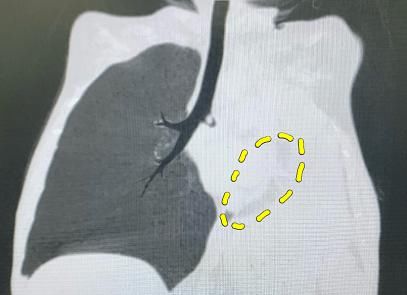

医生再次复查胸片和CT,发现球球的左肺出现了大“麻烦”,正常人的两侧的肺像气球一样,随着呼吸会完全膨胀,但球球左侧整个肺不仅没有涨起来,反而已经挛缩成一团。

左肺已经严重萎缩。